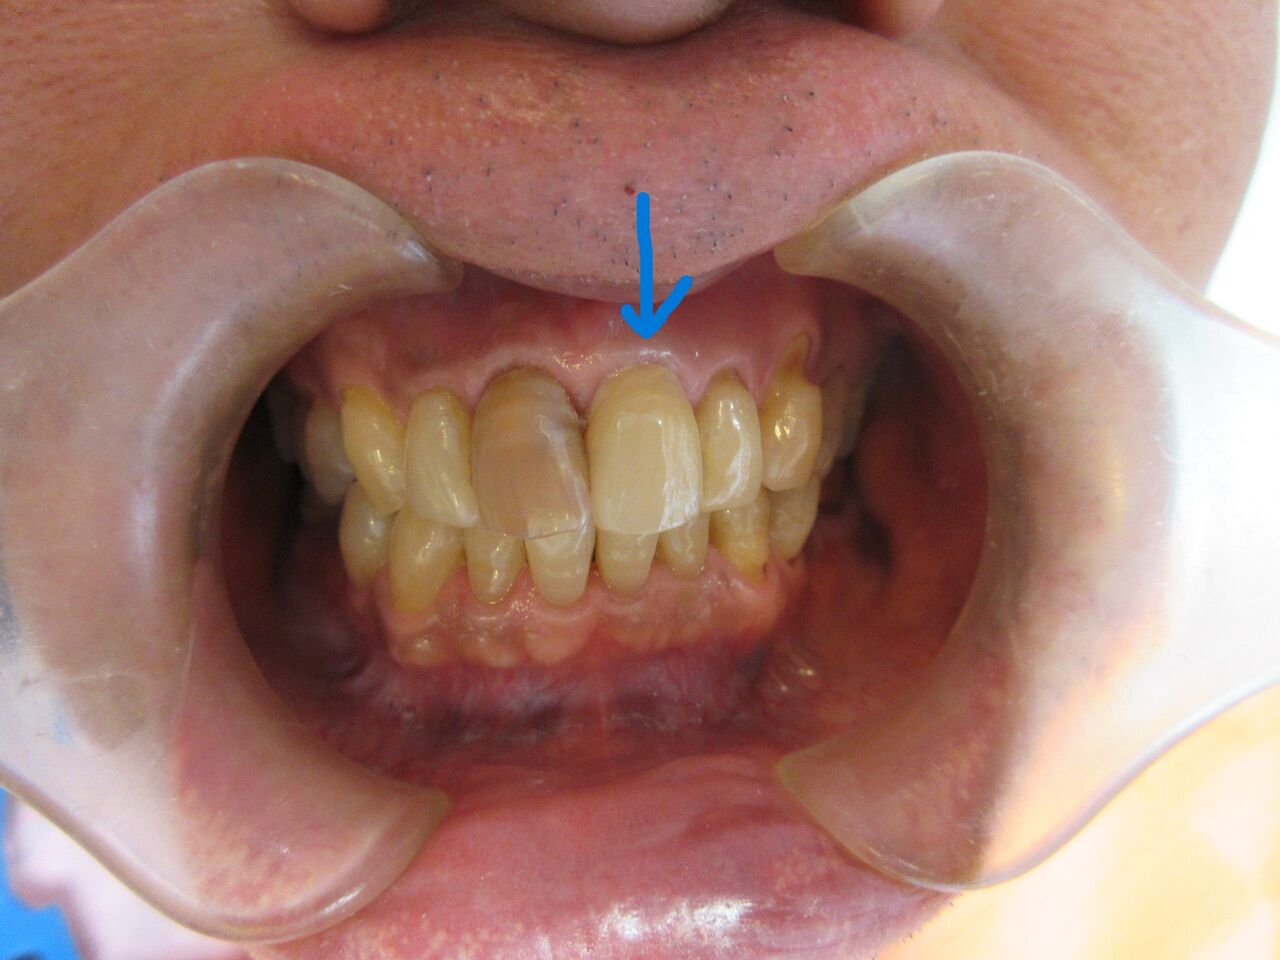

折れてしまった歯をオールセラミックで仕上げました。

反対側はブリーチングで白くする予定です。